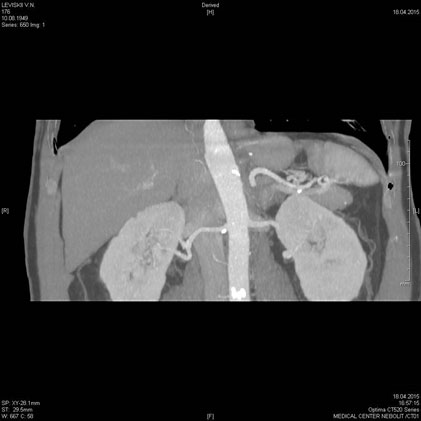

МСКТ почек, надпочечников

- Дифференциальная диагностика объемных образований почек

- Стадирование опухолей

- Стенозы почечных артерий

- Почечная колика без контрастирования

- Обструкции мочеточников

МСКТ надпочечников, почек

Показания:

- подозрение на опухоль почек, надпочечников, забрюшинного пространства

- травма почек

- воспалительное поражение почек и паранефральной клетчатки